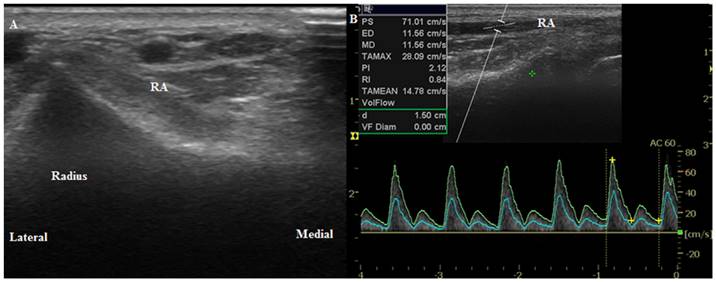

The wrist joint of each patient was extended up to 45° on a wrist board as described in a study by Mizukoshi et al. [9] We selected the cannulation position where the most prominent radial artery pulsation around the radial styloid process occurred. Using B-mode ultrasound, we placed the probe axially 1 cm proximal to the marked point to measure the anterior-posterior internal diameter of the radial and ulnar arteries. We then perpendicularly placed the probe to obtain a circular image of the artery (Figure 1A, 2A). We measured the peak systolic velocity (PSV), end-diastolic velocity (EDV), resistance index (RI, RI = [PSV-EDV]/PSV), and mean volume flow (MVF) directly from a longitudinal duplex Doppler spectral waveform with an angle correction of 60° (Figure 1B, 2B). Vessel compression was minimized using a conductive gel with decreased pressure on the probe. We collected transverse sections of the radial artery proximal to the presumed puncture site to obtain maximal diameter measurements and clear visualization of the arteries' internal lumen. Every image was acquired in triplicate.

Figure 1

Ultrasound images of the radial artery. (A) Transverse circular image of the radial artery before anesthesia induction (T0). (B) Longitudinal duplex Dopppler spectral waveform with an angle correction of 60°. RA, radial artery.

Int J Med Sci Image